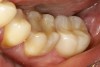

The CompoMaster polisher (Shofu Dental Corporation) simple two-step system produced a smooth finish. Dura-Polish (Shofu Dental Corporation) impregnated with aluminum oxide was used with a Robinson's #11 soft bristle brush to polish the crown. Dura-Polish DIA impregnated with diamond particles was used with a felt wheel to super polish the crown to a high luster. The intaglio of the crown was treated with 50-μm aluminum oxide sandblasting, ultrasonic (water bath), ethanol cleaning, and Shofu HC Primer. Cementation was achieved by etching the tooth structure, applying Clearfil SE Bond 2 and Clearfil DC Activator (Kuraray), and using MonoCem (Shofu Dental Corporation) as a permanent cement. Adjustment and polishing were done quickly and easily (Figure 4).

Shofu's Block HC was an effective option for this patient. All the materials supported the procedure to restore a permanent single crown that successfully met patient expectations. Tooth No. 18 is fully functional with an outstanding esthetic result (Figure 5). Shofu's novel hybrid ceramic is an alternative to restore crowns on any patient, especially for those with severe tooth erosion and minimal tooth structure. It can provide a canvas for artistry and beauty in rehabilitating the tooth to its original function.

Fig 4. The adjustment and polishing of the Shofu Block HC was easy and quick.

Figure 4

Fig 5. Tooth No. 18 is fully functional with an outstanding esthetic result.

Figure 5